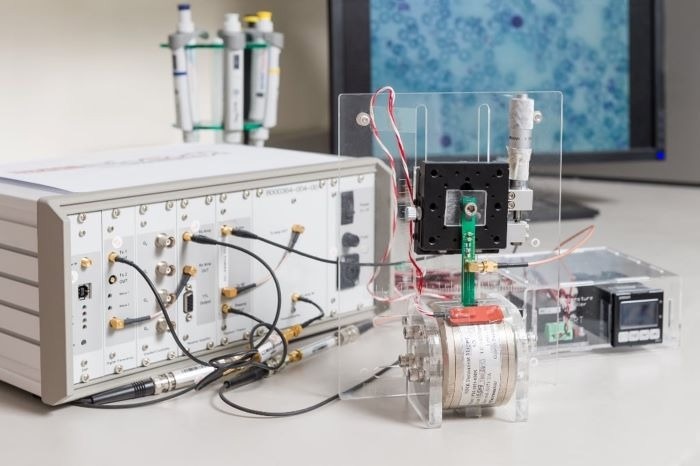

חוקרים מה-Critical Analytics for Manufacturing Personalized-Medicine (CAMP) Interdisciplinary Research Group (IRG) ב-Singapore-MIT Alliance for Research and Technology (SMART), מפעל המחקר